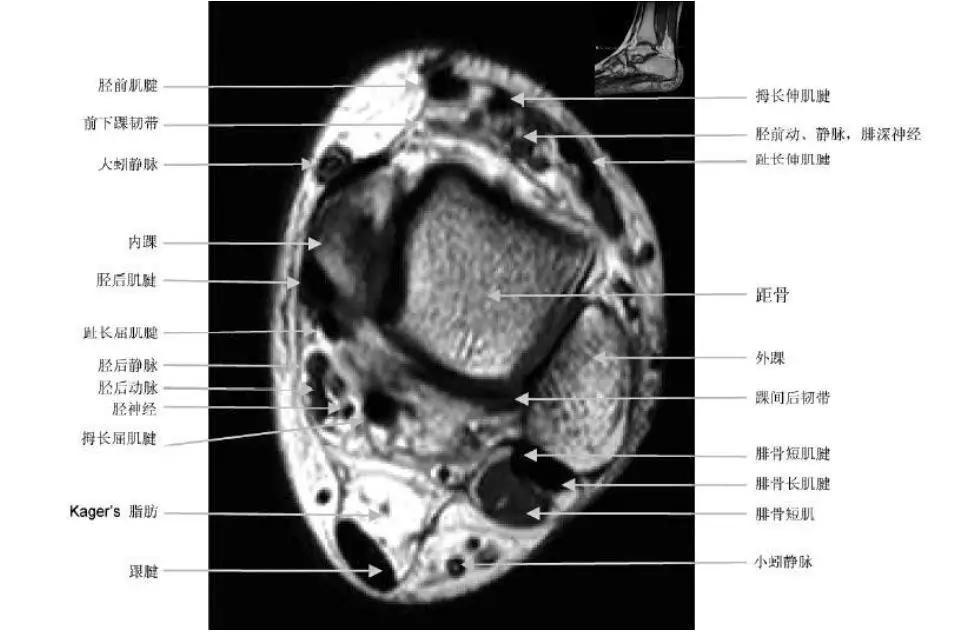

- 外侧:腓骨长肌和腓骨短肌;

- 内侧:胫骨后肌,拇长屈肌,趾长屈肌;

- 前侧:胫骨前肌,拇长伸肌,趾长伸肌;

- 后侧:跟腱。